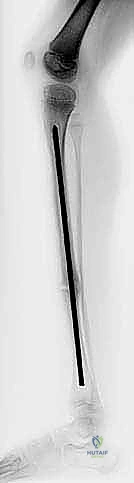

الالتحام الكاذب الخلقي في قصبة الساق هو كسر مرضي يمنع التئام العظم بشكل طبيعي. يتضمن العلاج الفعال تثبيت قصبة الساق باستخدام قضيب ويليامز داخل النخاع، وهي جراحة دقيقة تهدف إلى استعادة وظيفة الساق وتقليل التشوهات لتحقيق المشي الطبيعي.

الخلاصة الطبية السريعة: الالتحام الكاذب الخلقي في قصبة الساق (Congenital Pseudarthrosis of the Tibia) هو حالة مَرَضية معقدة وكسر غير طبيعي يمنع التئام العظم بشكل تلقائي، وغالباً ما يُكتشف في السنوات الأولى من عمر الطفل. يتضمن العلاج الجراحي الفعال والأكثر تطوراً تثبيت قصبة الساق باستخدام "قضيب ويليامز" (Williams Rod) داخل النخاع. تُعد هذه الجراحة الدقيقة، التي تتطلب مهارة استثنائية، الحل الأمثل لاستعادة الوظيفة الحركية للساق، تصحيح التشوهات، وتحقيق حلم المشي الطبيعي للطفل.

تتعدد التقنيات الجراحية (مثل جهاز إليزاروف الخارجي، أو الصفائح المعدنية)، ولكن التثبيت داخل النخاع (Intramedullary Nailing) أثبت أنه الأنجح على المدى الطويل. ومن بين هذه القضبان، يبرز قضيب ويليامز.

1. الصلابة والمرونة: يوفر دعماً ميكانيكياً داخلياً هائلاً يمنع إعادة الكسر، ولكنه يمتلك مرونة كافية لتوزيع الأحمال الحركية.

2. حماية صفائح النمو: تم تصميم نهايات القضيب بطريقة تقلل من تدمير صفائح النمو عند الأطفال، مما يسمح للعظم بالاستمرار في النمو الطولي.

3. التوجيه (Alignment): يعمل كدعامة داخلية تجبر العظم على النمو بشكل مستقيم، مانعاً تكرار الانحناء الأمامي.

الخطوة الخامسة: إدخال قضيب ويليامز

يتم اختيار قضيب ويليامز بالطول والسمك المناسبين بناءً على قياسات دقيقة. يتم إدخال القضيب من أعلى قصبة الساق (قرب الركبة) أو من أسفلها، ليخترق القناة النخاعية، ويعبر منطقة الكسر، ليصل إلى الجزء الآخر من العظم، مما يضمن استقامة الساق وتثبيت الكسر بقوة.